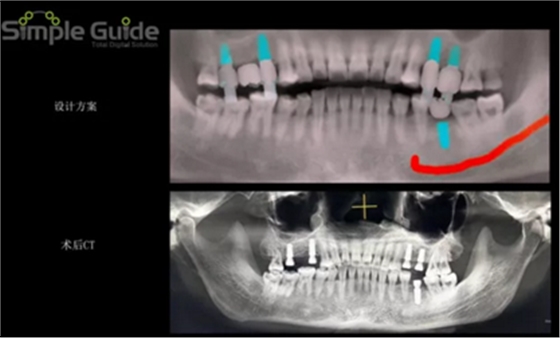

種植規(guī)劃與術(shù)后CBCT影像對比

繪制下頜神經(jīng)管

植體植入設(shè)計

設(shè)計植入5顆種植體